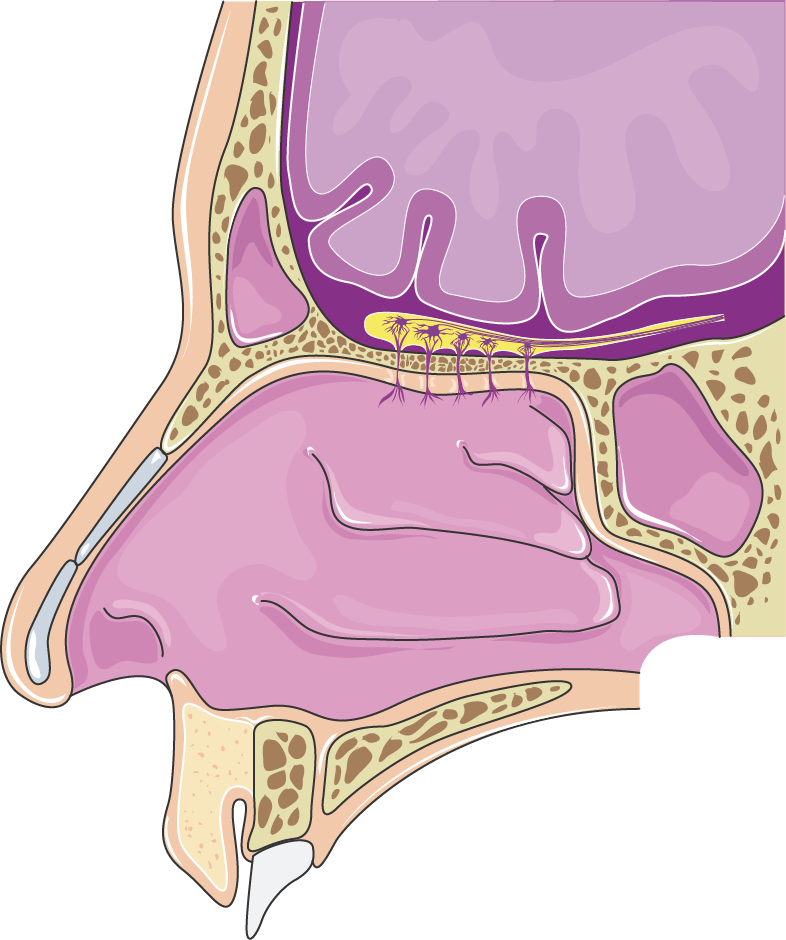

Is your nose also an excretory organ? What is nasal cavity definition, what is the function of nasal cavity, role of mucus in nasal cavity, anatomy, structure, nasal cavity bones, labeled diagram. Introduction:the nasal cavities are the uppermost parts of the. The nasal cavity (or nasal fossa) is a large air filled space above and behind the nose in the middle of the face. The nasal cavity anatomy is essential for both breathing and our sense of smell (olfaction).

Try to ascertain how much is bony and how much cartilaginous. Primary nasal cavity tumors often originate on the nasal septum or roof of the nasal vault and will acr appropriateness criteria®. Gross anatomy the nasal cavity is formed by 1: The nasal vestibule, the nasal cavity proper or nasal fossa, and the olfactory region.4 the nasal vestibules are the two entry points into the nasal cavity. Inside your nasal cavity, you have 4 types of paranasal sinuses, usually called sinuses (see figure 1). Their locations and structures are best viewed when the head is shown in sagittal section. The nasal cavity is divided into three regions: The nasal cavity (or nasal fossa) is a large air filled space above and behind the nose in the middle of the face.

That is why food is almost tasteless when. The nasal cavity (or cavity of nose, latin: • separated by a midline nasal septum. The nasal cavity refers to the interior of the nose, or the structure which opens exteriorly at the nostrils. • each nasal cavity has a floor, roof, medial wall • lateral to the nasal cavities are the orbits. Primary nasal cavity tumors often originate on the nasal septum or roof of the nasal vault and will acr appropriateness criteria®. Inferior, middle and superior nasal conchae (turbinates). The respiratory tract begins with the nose which includes the external nose, internal nasal cavities and paranasal sinuses. Learn about nasal cavity with free interactive flashcards. Choose from 500 different sets of flashcards about nasal cavity on quizlet. The nasal cavity is located just behind the two nostrils and forms the inside of the nose. Other articles where nasal cavity is discussed: The nasal cavity anatomy is essential for both breathing and our sense of smell (olfaction).

It is the entry point for inspired air and the first of a series of structures which form the respiratory. That is why food is almost tasteless when. Inside your nasal cavity, you have 4 types of paranasal sinuses, usually called sinuses (see figure 1). Primary nasal cavity tumors often originate on the nasal septum or roof of the nasal vault and will acr appropriateness criteria®. Learn about nasal cavity with free interactive flashcards. The respiratory tract begins with the nose which includes the external nose, internal nasal cavities and paranasal sinuses. The nasal cavity is divided into three regions: The nose and nasal cavity make up the first portion of the upper respiratory tract. Nasal cavity facts, function, parts and diseases, a comprehensive study. Is your nose also an excretory organ? • each nasal cavity has a floor, roof, medial wall • lateral to the nasal cavities are the orbits. A region which communicates with the nasopharynx via a choana. Examine the nasal septum (953/n35).

Introduction:the nasal cavities are the uppermost parts of the. Try to ascertain how much is bony and how much cartilaginous. • separated by a midline nasal septum. Lower end of nasal bone. It constitutes the upper respiratory system along with the paranasal sinuses , oral cavity, pharynx and larynx, and. Lateral wall of the nasal cavity; • from oral cavity below by the hard palate. Nasal cavity facts, function, parts and diseases, a comprehensive study.